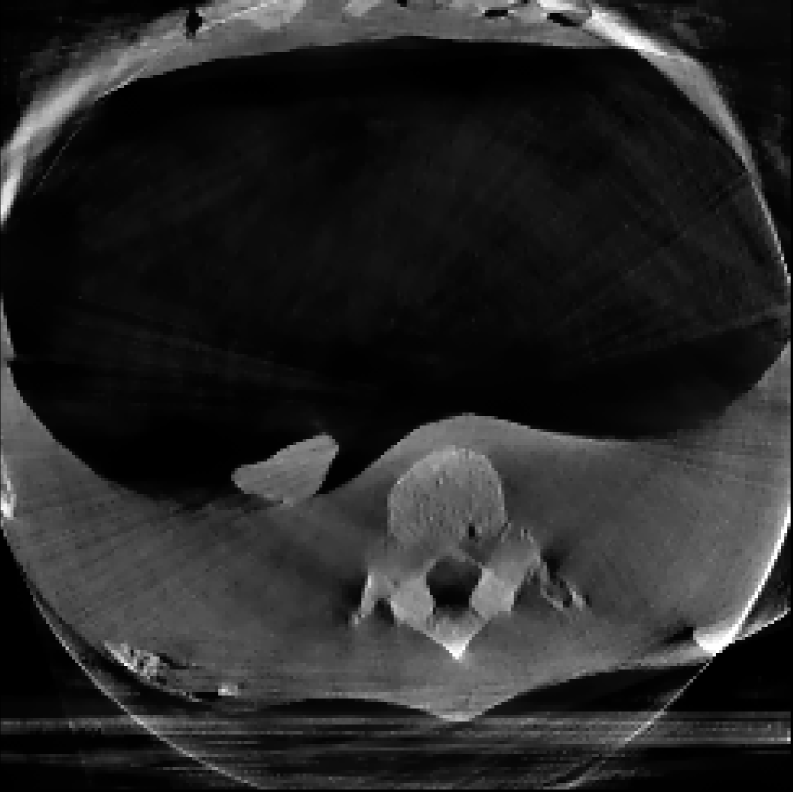

3.2 Lung Needle Surgery Scan:

In this example, we reconstruct a Thorax phantom scanned using the Phillips Allura FD20 Xper C-arm CBCT scanner. This device has source-to-axis and source-to-detector distances of 810 mm and 1195 mm respectively, and an installed detector of size 30×\times40 cm2 with 0.776 mm pixel pitch. Moreover, the data has a resolution of 364×512×364\times 512\timesnumber of projections and the image is reconstructed with a resolution of 256×256×256256\times 256\times 256 voxels.

The reconstructions corresponding to the real-scan data with different number of projections (180, 50, and 20, respectively), can be observed in Figures 3, 4, and 5. In all three figures (a) is the prior image 𝒙p\boldsymbol{x}_{p} used for prior image regularization, (f) is the ground truth image; and the rest of images correspond to different reconstructions (top) with their corresponding errors (bottom). Analogously to the previous experiment, the difference images (or error) should be completely black in the case of a perfect reconstruction and high intensity indicates more inaccurate reconstructions.

Note that the real data contains a lot of measurement noise, and due to the presence of the needle, the reconstructions can suffer from strong metal artifacts. Therefore, the reconstructed images using different algorithms, particularly without explicit regularization, tend to show strong errors even with a high number of projections. Accordingly, all the algorithms with explicit regularization perform better in this scenario, and particularly those including PIPLE or PICCS regularization. Moreover, the proposed IRN-PIPLE algorithm significantly outperforms other methods, and IRN-PICCS is not far behind. Using only TV regularization struggles to separate artifacts from features, oversmoothing images and thus loosing important image features. Notably, the proposed methods reconstruct high quality images in less than 2 minutes in an implementation that is not optimized to solve this specific geometry.

Figure 3: Reconstructed images using real measurements of a thorax phantom with 180 projection. The reconstructed images are shown in [0, 0.03]; difference images in [–0.04, 0.04].